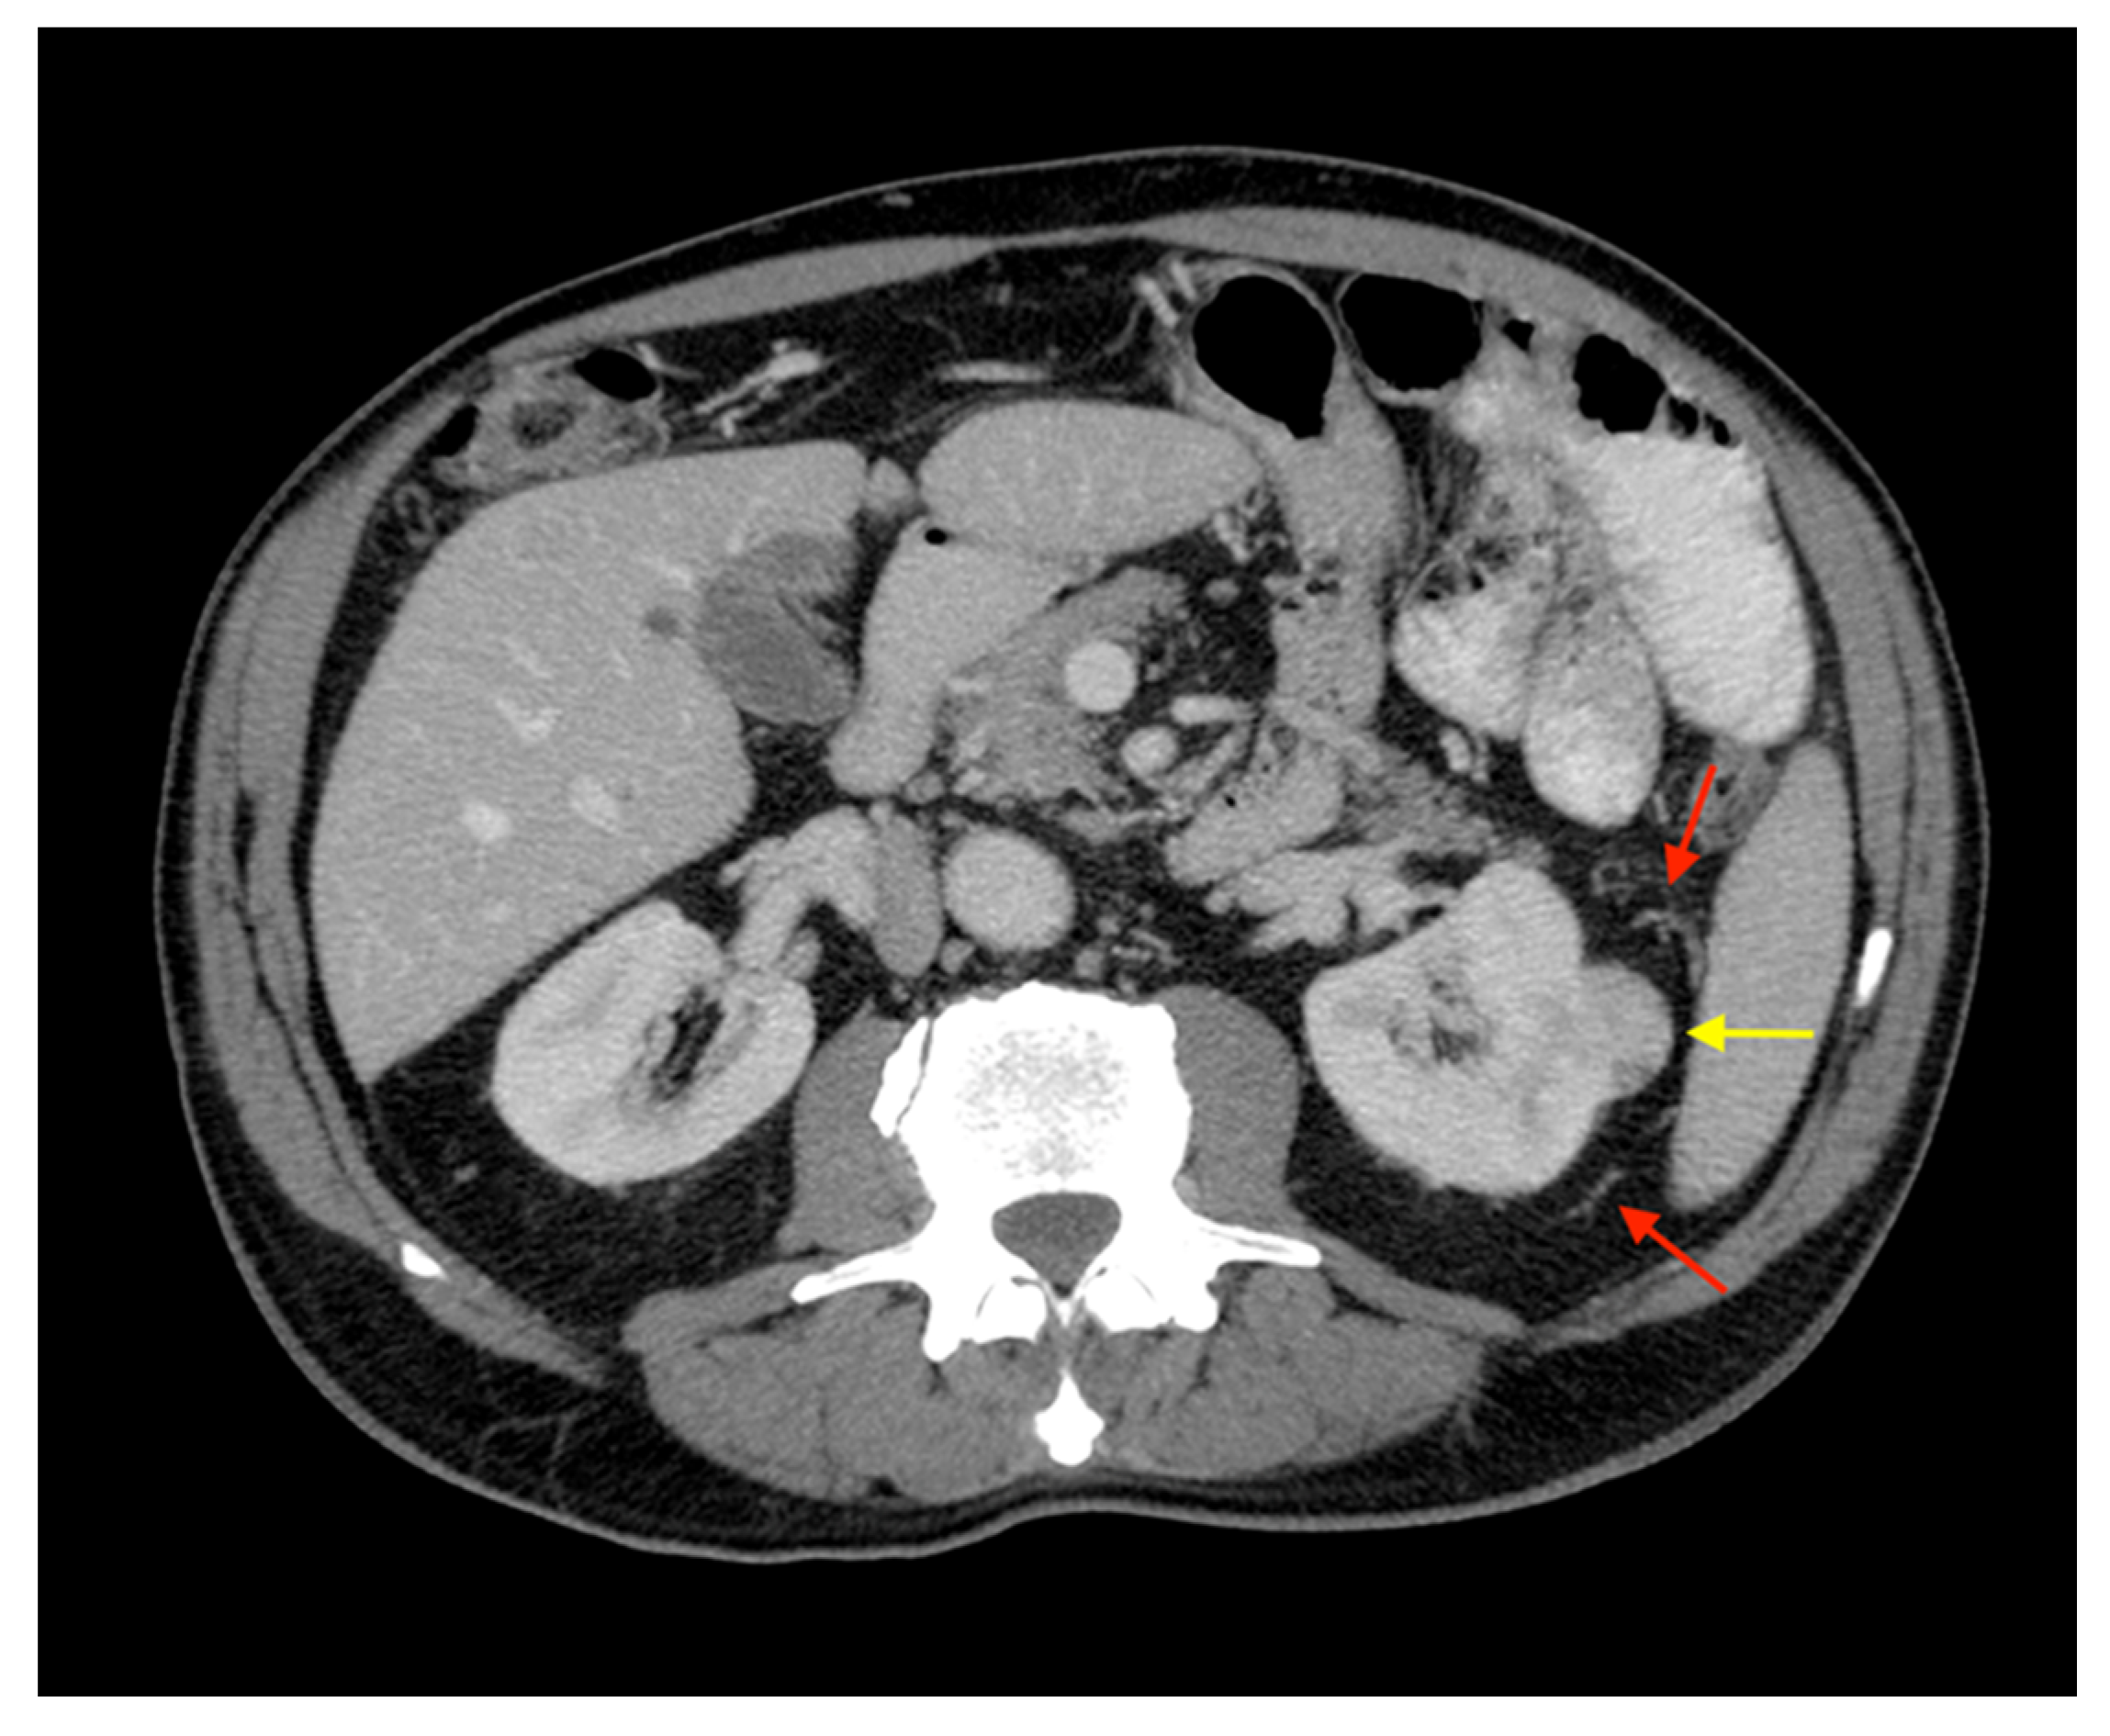

The presence of collateral vessels in renal cell carcinoma (RCC) is considered a sign of locally advanced disease (i.e., pT stage > T3a) [12]. However, this finding can be present in the early stages of RCC (Figure 1).

Figure 1.

Axial CT image with maximum intensity projection (MIP) reconstruction showing ccRCC with T1a of locoregional staging (yellow arrow) and peritumoral collateral vessels (red arrows). Note that peritumoral collateral vessels can be present also in patients with early disease stages.